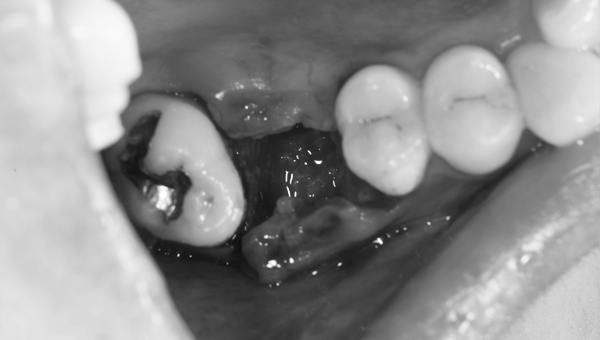

歯が大きく欠けた

歯ぐきが治癒した

説明:

右上の歯が大きく欠けています。黒く虫歯になっているのがわかります。移植を計画しましたので、歯ぐきがしっかり治癒するのを(1ヶ月)待ちました。

手術前

手術中

歯ぐきを切り、骨の状態を確認します。移植する歯が入るためのスペースを作るために、骨を歯が入るように削っていきます。